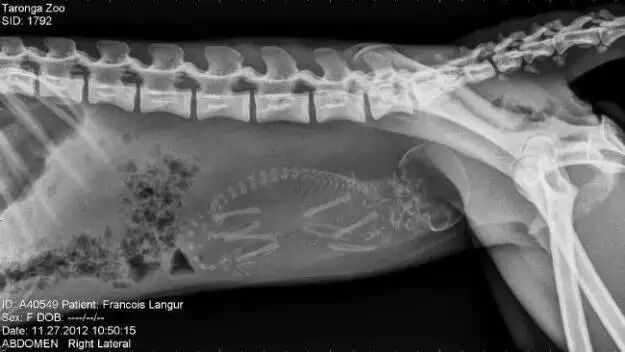

NO.13

<怀孕的猴子>

简直和人类一毛一样啊⊙▽⊙

咳咳,毕竟我们人类,

是猴子进化来的嘛~